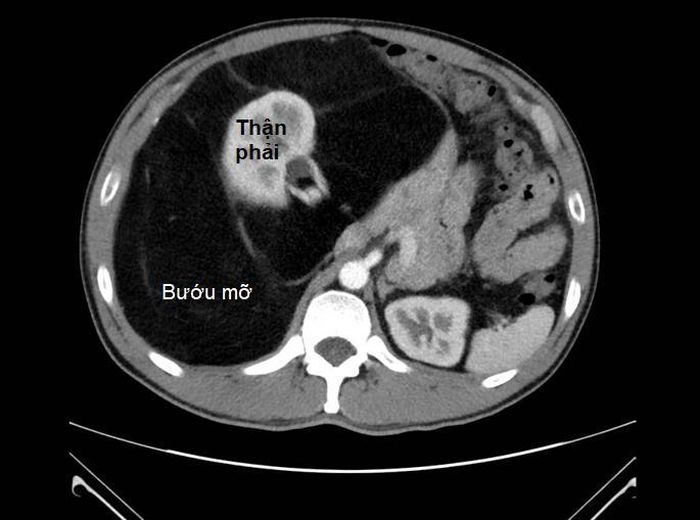

Bướu mỡ đường kính 40 cm bao xung quanh thận phải. Ảnh: BV

BS.CKII. Nguyễn Phúc Minh, Trưởng khoa Ngoại tiêu hóa là người trực tiếp phẫu thuật cho bệnh nhân T cho biết: “Qua kết quả chụp MRI bụng, khối bướu có đường kính lên đến 40 cm, cấu trúc tương đồng với mô mỡ, chiếm gần toàn bộ ổ bụng và bao quanh thận phải. Nghiêm trọng hơn, khối bướu dính và chèn ép các mạch máu lớn như động mạch, tĩnh mạch chủ bụng và các mạch máu lân cận làm suy giảm chức năng thận”.